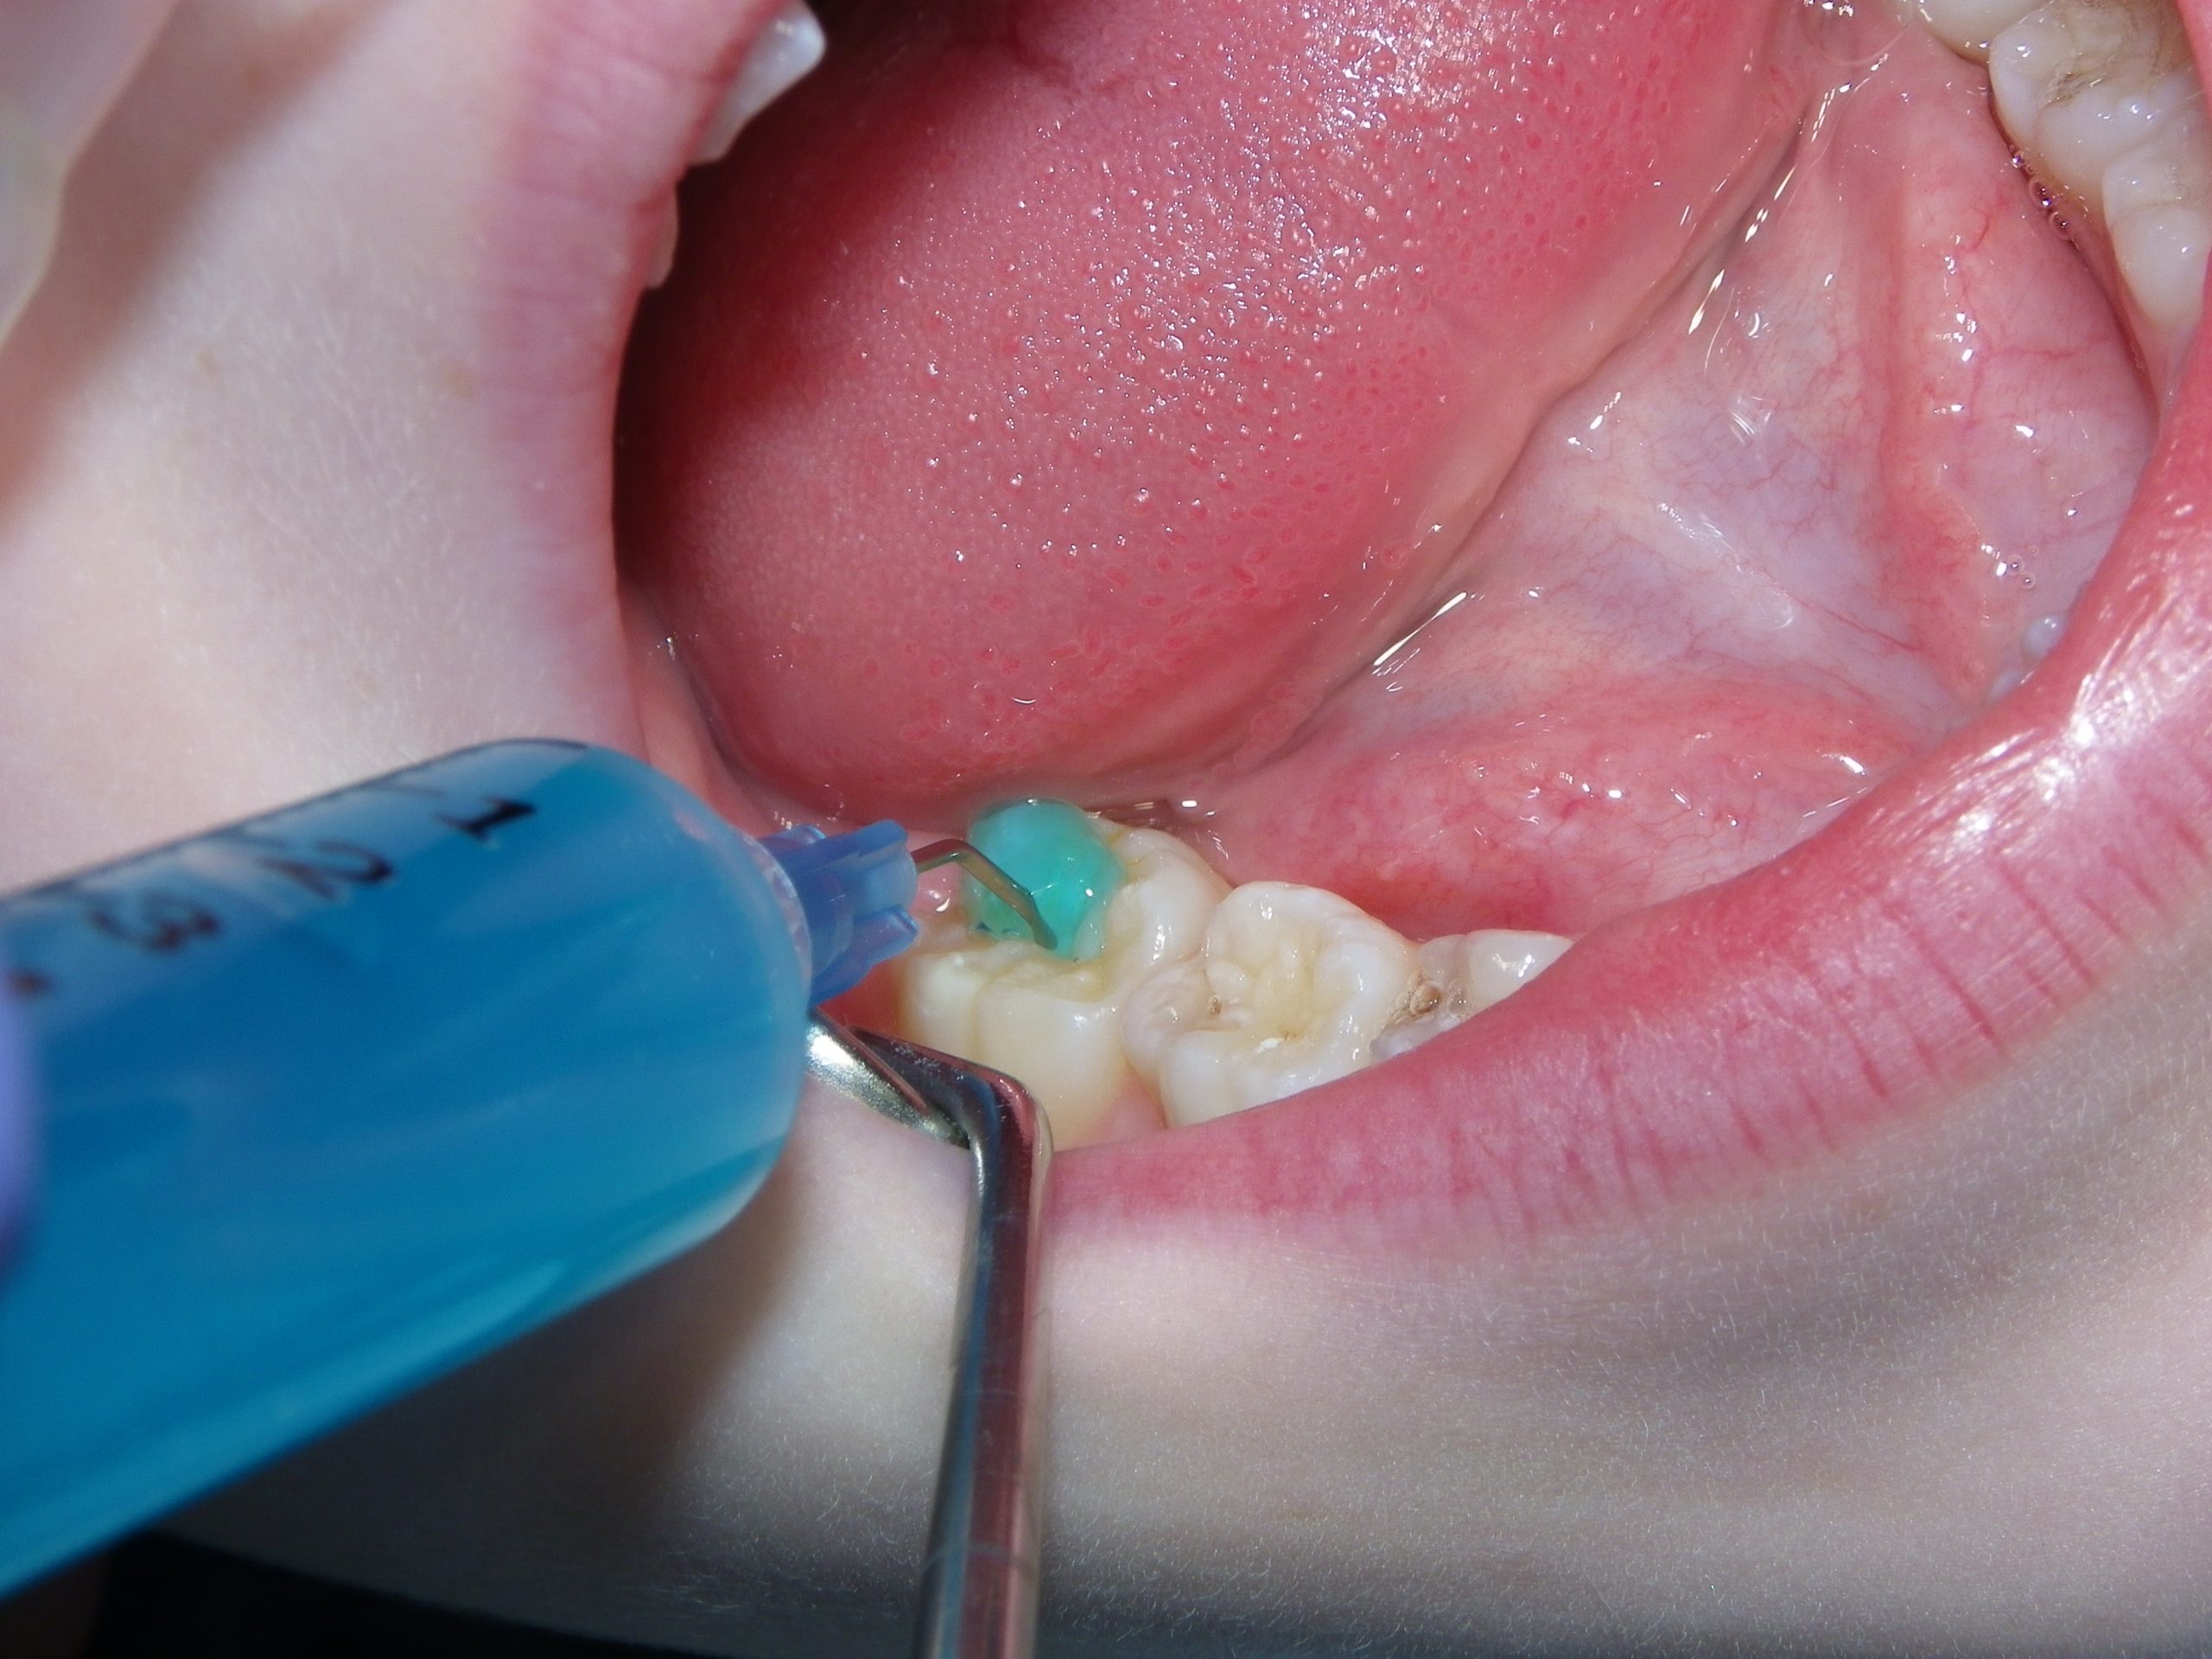

This quick photo series shows the step-by-step process of placing a sealant onto the grooves of an adult molar of a six-year-old. First, air abrasion is used to mechanically remove any loose surface debris or contaminants. Secondly, an acid gel is applied to the surface to be sealed. Finally, a sealant is applied to the surface and allowed to set. For the sharp-eyed, the sealant used was GC Fuji Triage, a glass ionomer sealant that while not as wear-resistant as the more commonly used resin sealants, is more moisture-friendly (ie: contamination resistant) and releases fluoride. The fluoride release allows the underlying enamel to be strengthened over time, making it more decay-resistant for the future.